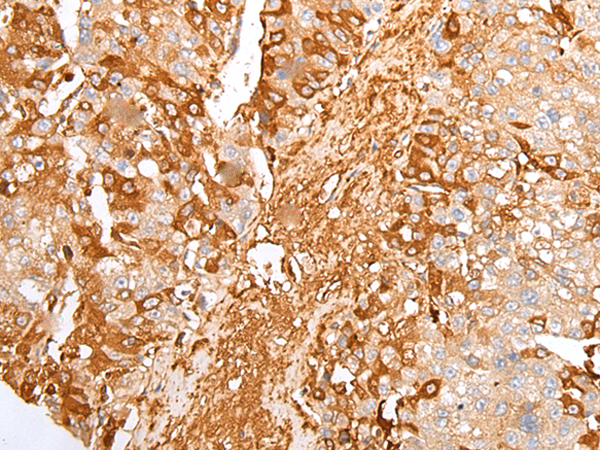

ELISA, IHC |

IHC positive control: |

Human liver cancer and Human cervical cancer |

IHC Recommend dilution: |

25-100 |